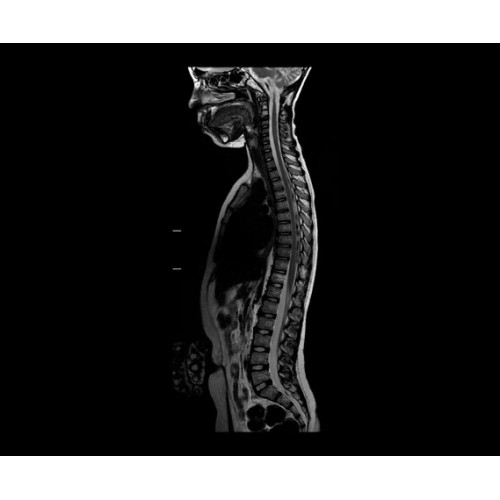

SIGNA PET/MR 3.0T — это гибридная система, в которой совмещаются две принципиально разные технологии — магнитно-резонансную томографию (МРТ) и позитронно-эмиссионную томографию (ПЭТ). Система отличающийся высокой чувствительностью и эффективностью и предназначена для диагностики в области онкологии, неврологии, кардио-васкулярных исследований, исследований воспалительных процессов.

Компания GE Healthcare представляет революционную, полностью интегрированную систему SIGNA PET/MR1, в которой сочетаются времяпролетная технология (TOF) и возможности напряженности магнитного поля 3.0 Тл. Мы поможем вам поднять исследования на более высокий уровень. SIGNA PET/MR позволяет достичь впечатляющей точности и скорости исследований, а благодаря новейшей технологии реконструкции Q.Clear2 качество изображений улучшается в два раза. Кроме того, в систему включен полный набор клинических приложений и гибких катушек для проведения любых видов исследования, открывая для вас возможности визуализации, о которых вы даже не догадывались.

В систему SIGNA PET/MR встроены запатентованные детекторы кремниевого фотоумножителя (SiPM) и сверхчувствительные кристаллические сцинтилляторы на основе лютеция толщиной 25 мм. Благодаря этому обеспечивается исключительная чувствительность и возможность использования времяпролетной диагностики (TOF).